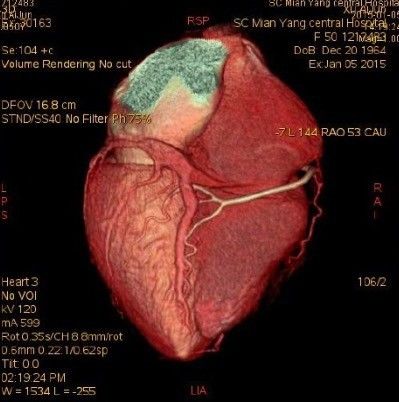

3、VRT(容积成像)不需要重建物体的表面几何信息,通过计算体素的阻光度、颜色、梯度等,然后直接把三维灰度数据投影到二维屏幕上,在投影时累计半透明体素对光线的透射吸收作用。它是目前的常用方法。它保持原图像所有信息,同时显示空间结构和密度信息。